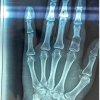

X-rays revealed cystic expansion and cortical thinning [3] of the proximal phalanges with lytic lesions (Fig. 2). Computed tomography imaging confirmed cortical destruction and periosteal reaction (Fig. 3).

Figure 2: X-ray B/L hands showing involvement of phalanx.